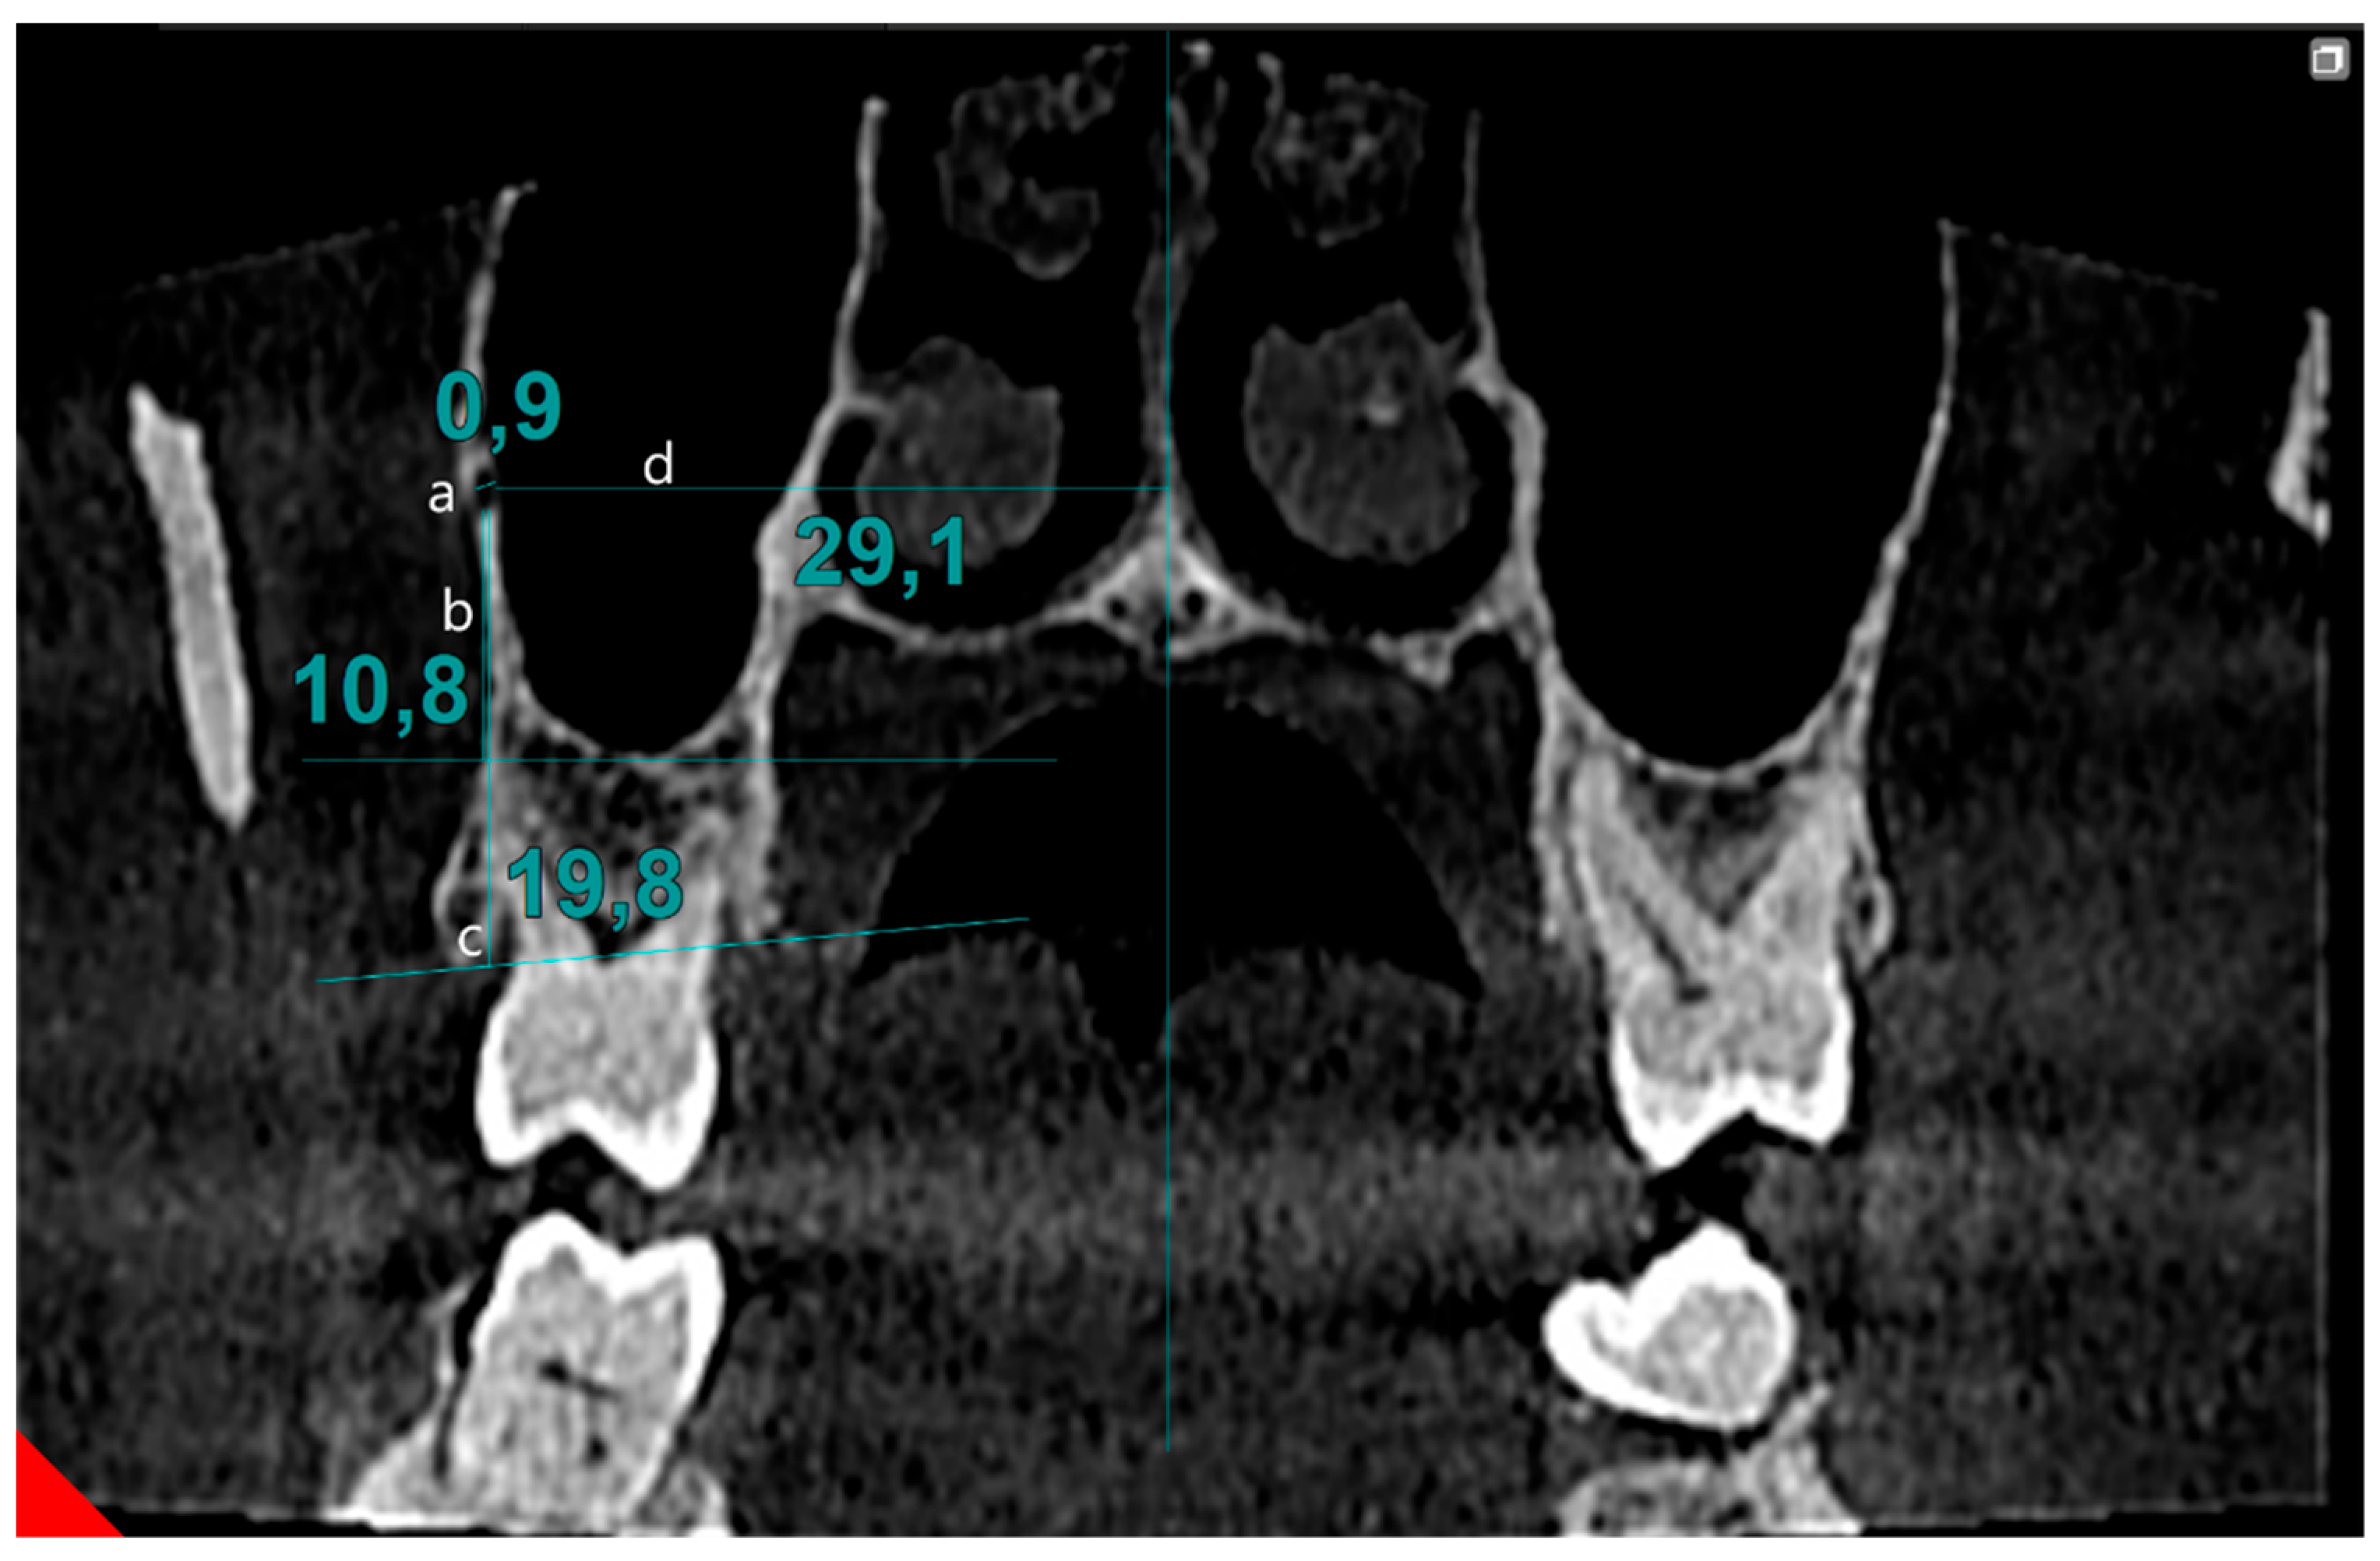

| Diameter | 0.84 ± 0.25 0.80 (0.3–2.1) | 0.82 ± 0.22 0.80 (0.3–1.5) | 0.690 |

| Distance to maxillary sinus floor | 9.99 ± 3.41 9.90 (1.8–18.9) | 9.66 ± 3.59 9.60 (1.2–19.2) | 0.087 |

| Distance to alveolar crest | 18.67 ± 3.08 18.90 (9.3–27.3) | 18.17 ± 3.28 18.30 (8.4–27.6) | 0.013 * |

| Distance to nasal septum | 30.64 ± 2.16 30.60 (25.5–37.9) | 30.35 ± 2.13 30.30 (25.5–36.9) | 0.002 |

| Distance to nasal cavity floor | 13.20 ± 2.83 13.40 (6.3–20.3) | 13.47 ± 2.73 13.65 (6.3–18.8) | 0.464 |

| Distance to buccal bone | 7.04 ± 1.82 6.90 (3.0–13.5) | 7.20 ± 1.87 7.10 (1.5–13.8) | 0.538 |

| Distance to alveolar crest | 6.25 ± 2.55 5.55 (2.6–13.4) | 5.95 ± 2.05 5.70 (1.6–12.4) | 0.743 |